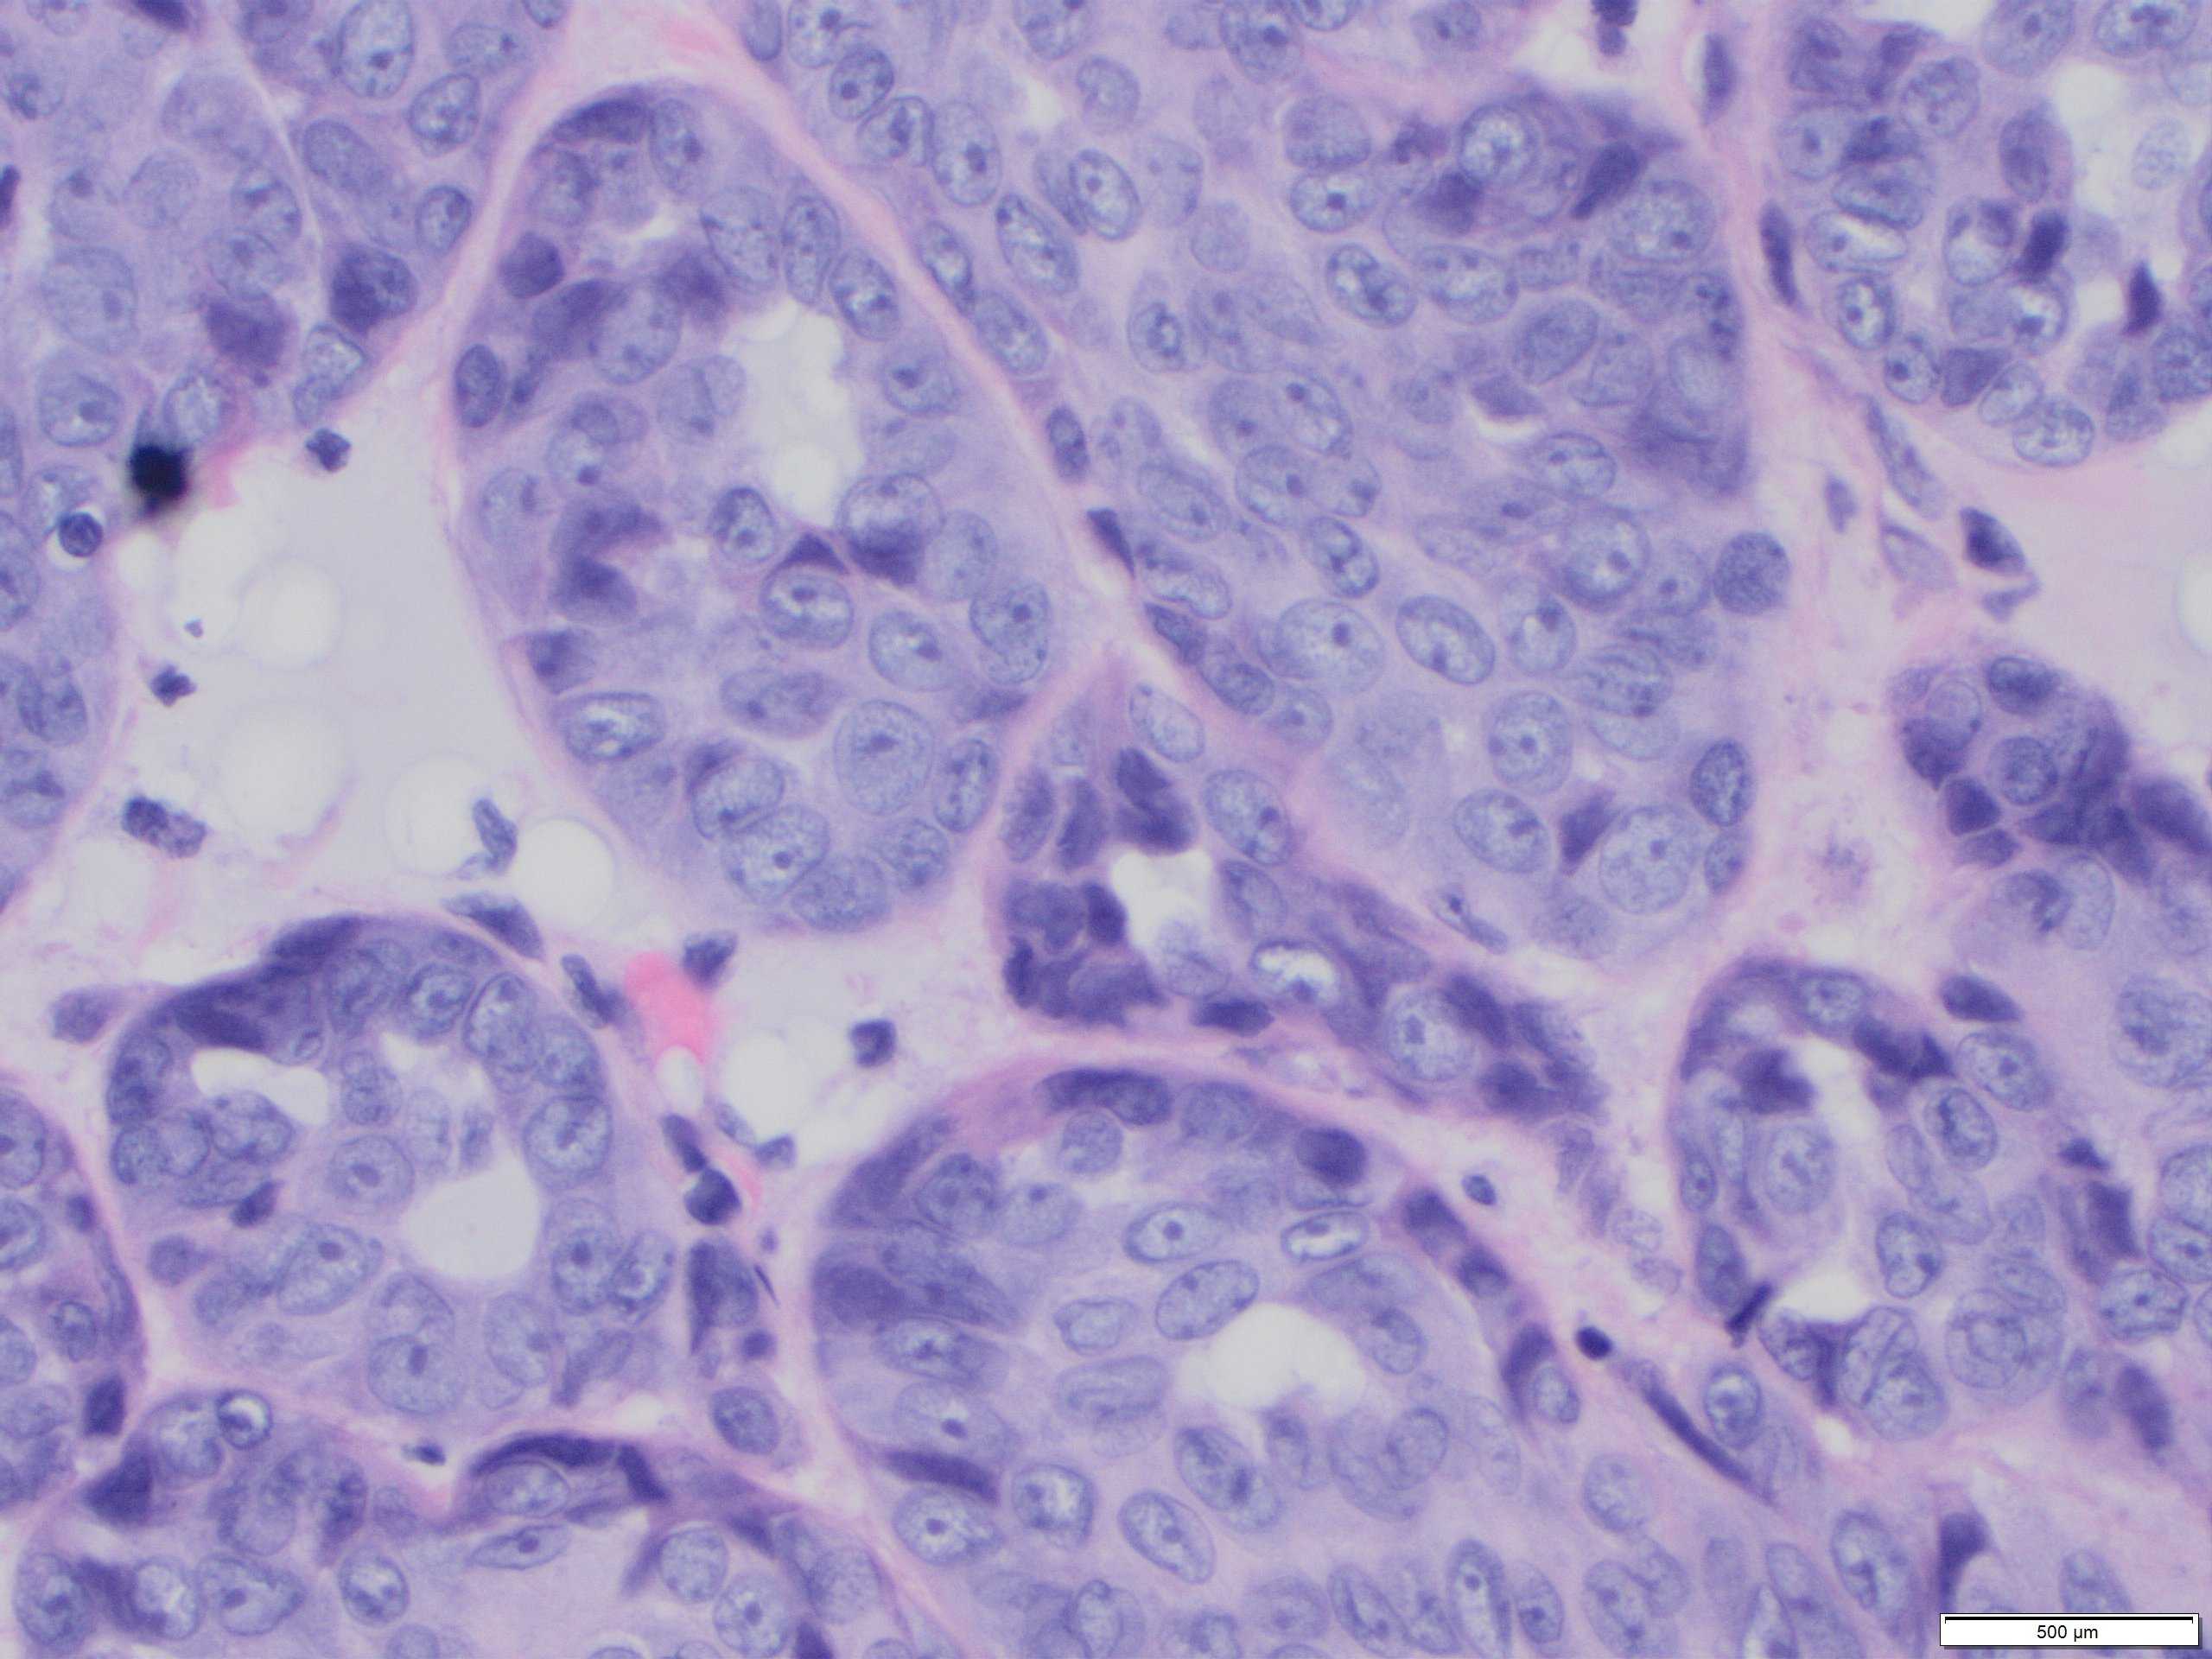

Classical benign AME comprises epithelial and myepithelial (MECs) with varying ratios within and between tumours. MECs usually dominate and are more numerous than the single basal layer component of the epithelial myoepithelial bilayer of normal breast lobules, adenosis nodules or simple papillomas. The cells are often small and uniform without cytological atypia or increased mitotic activity.

Malignant AME (M-AME) shows varied macroscopic appearances from a multilobulated, well-defined mass, similar to classic AME, to a poorly defined mass with infiltrative borders. Histological features of malignancy: overgrowth of the epithelial or myoepithelial component, mild to moderate cytological atypia, and increased mitotic activity with or without mildly infiltrative growth pattern, and/or focal necrosis.